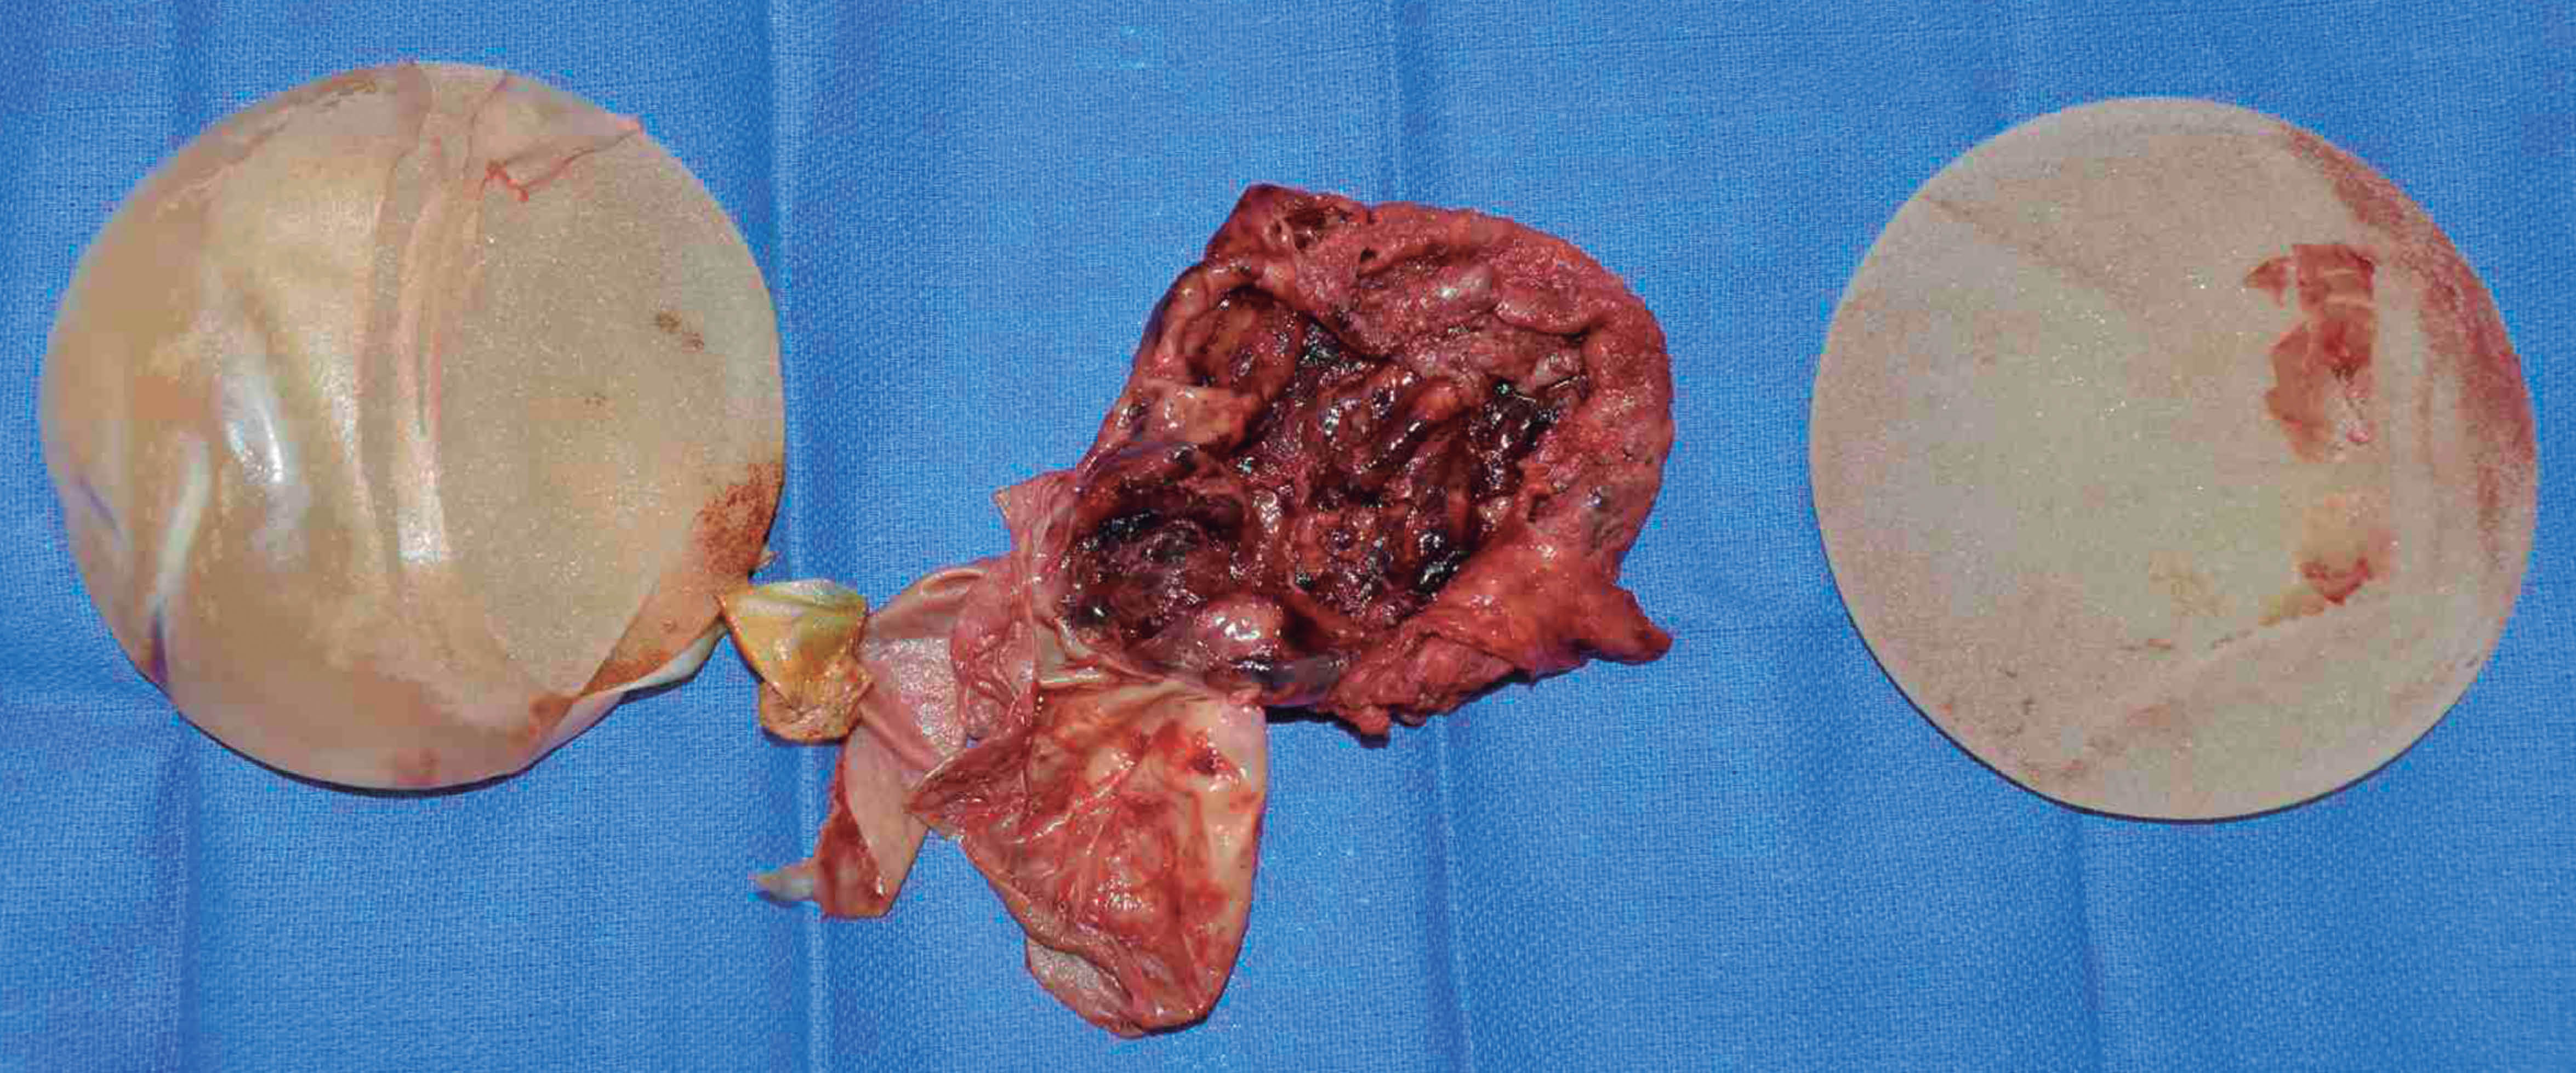

La paciente fue tratada con aspiraciones por aguja percutánea, guiada por ultrasonido en dos ocasiones. En el primer intento se drenó 500 mL; una semana después, en el segundo episodio, drenamos 300 mL y en este episodio se decidió junto con la paciente programar la extracción quirúrgica para mejorar los síntomas, misma que se realizó una semana después bajo anestesia general; drenamos 50 mL de hematoma, realizamos capsulectomía y reemplazo de implante mamario liso de 415 mL en el plano submuscular de las dos mamas, sin encontrar algún vaso sanguíneo con sangrado activo en el tejido capsular. No presentó complicaciones a los seis meses de seguimiento. El informe histopatológico de la cápsula mamaria izquierda (Figura 4) reportó cápsula fibrosa con proceso inflamatorio crónico severo (agregados linfoides no neoplásicos).

Figura 4